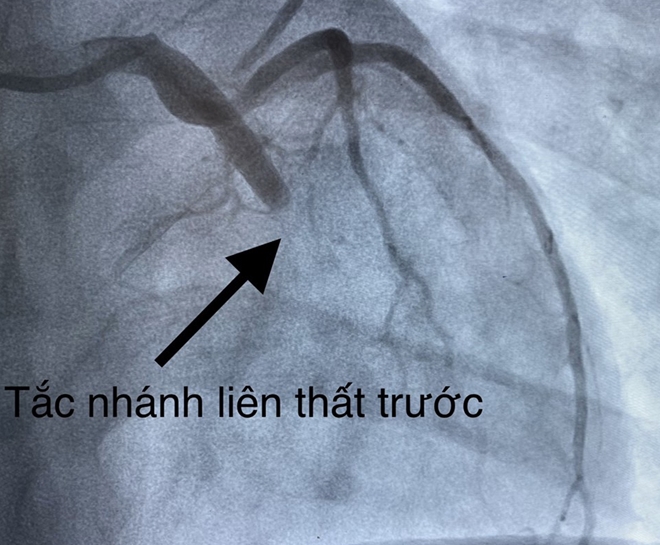

Hình ảnh bệnh nhân bị tắc liên thất trái.

Hội chẩn gồm nhiều chuyên khoa quyết định can thiệp cấp cứu tái thông mạch vành cho bệnh nhân. Ê kíp can thiệp do Ths.Bs Trần Văn Triệu, BS Dương Hoàng Mẫn tiến hành chụp mạch vành cấp cứu cho bệnh nhân. Kết quả chụp mạch vành tắc LADII – huyết khối mạch vành, ê kíp can thiệp nong bóng, đặt stent nhánh LADII .Thời gian can thiệp 15 phút.